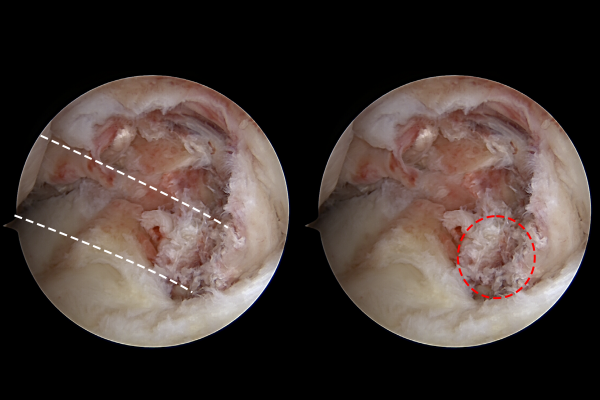

파열된 후방십자인대 재건을 위해 가이드를 삽입합니다.

후방십자인대를 재건할 길을 따라서 실을 잡아 올릴 수 있도록 가이드 와이어를 삽입합니다.